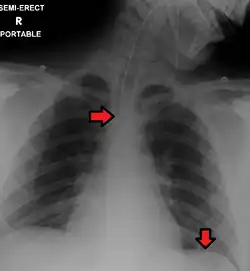

Placa de tórax tomada después de colocar un desfibrilador automático implantable; muestra el generador del aparato en el tórax superior izquierdo y la derivación (electrodo) del aparato en la cavidad del ventrículo derecho. Nótese ambos resortes radiopacos a lo largo de la derivación del aparato. -

Placa portátil (o sea, anteroposterior) mostrando tubo endotraqueal y tubo nasogástrico, ambos en correcta posición.